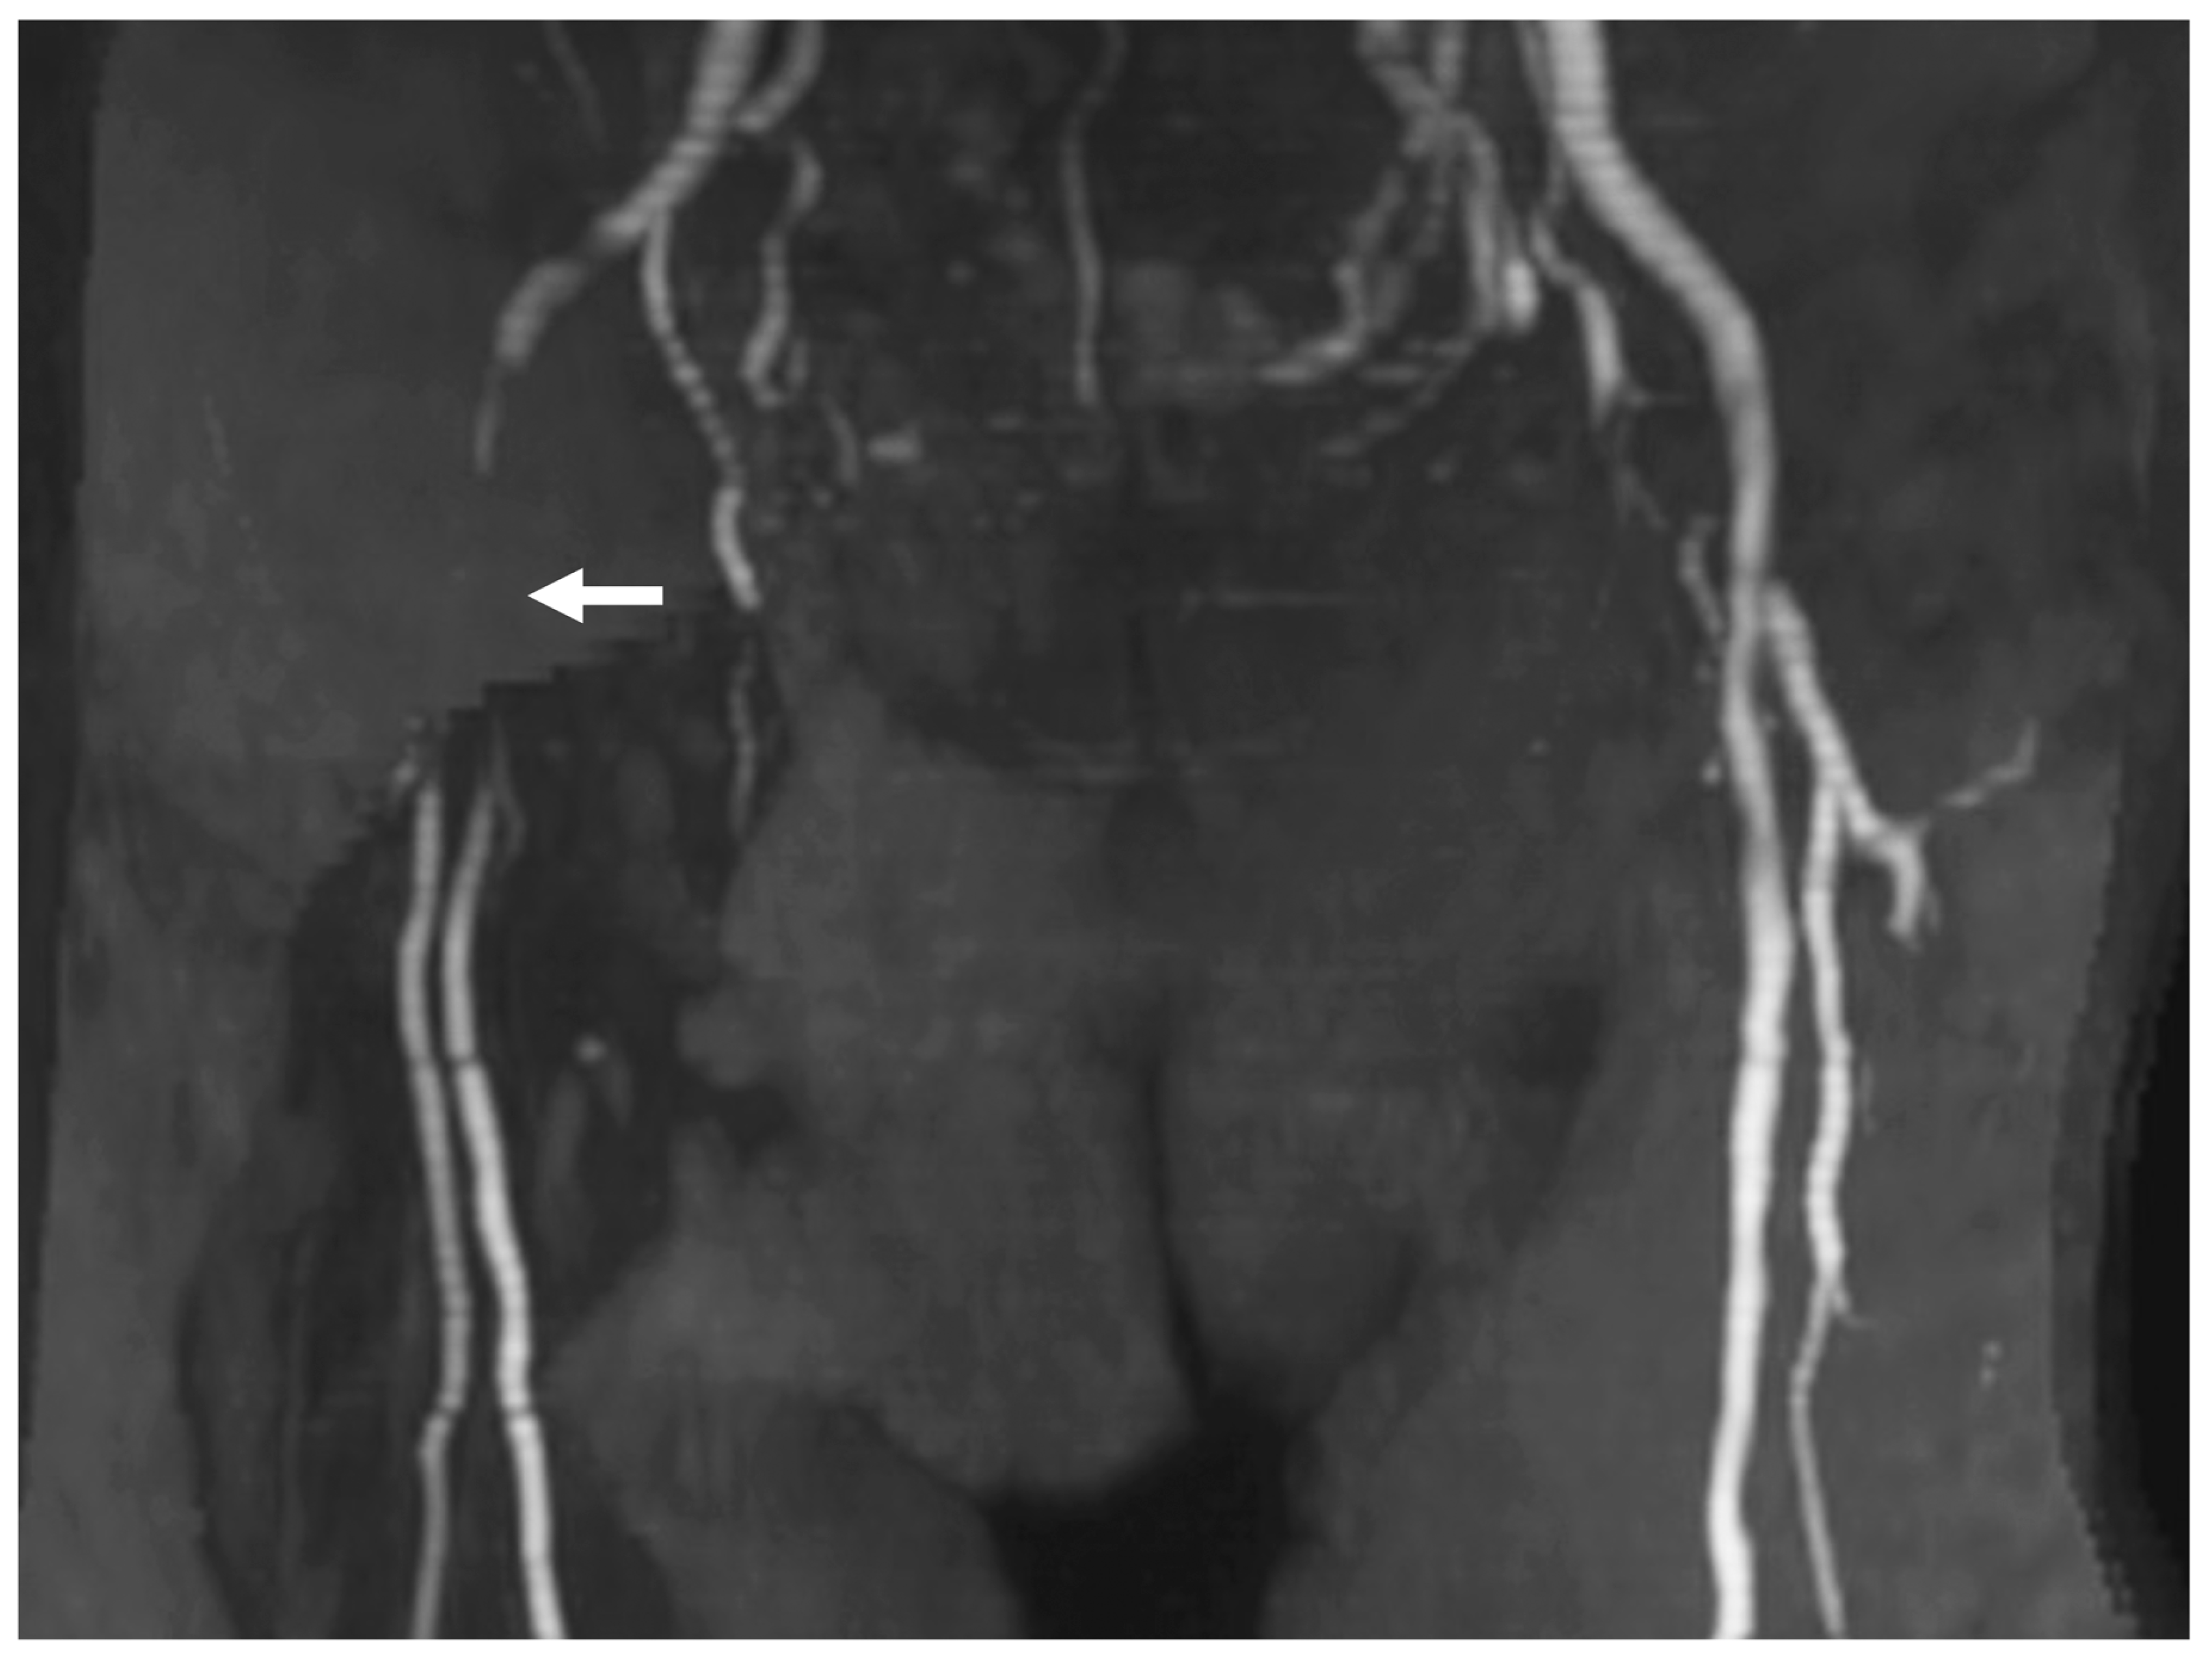

- Uno, T.; Shojima, M.; Oyama, Y.; Yamane, F.; Shin, M.; Matsuno, A. Anatomical factors that impede using the radial artery approach for carotid artery revascularization. World Neurosurg. 2022, 160, e398–e403. [Google Scholar] [CrossRef] [PubMed]